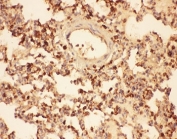

IHC-P testing of mouse lung tissue. HIER: steam section in pH6 citrate buffer for 20 min.

IHC-P testing of rat lung tissue. HIER: steam section in pH6 citrate buffer for 20 min.